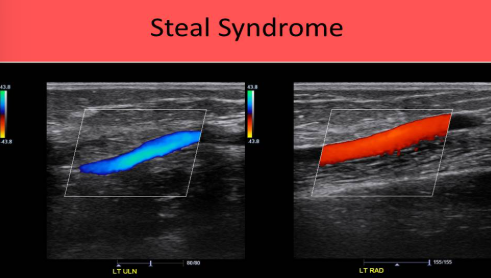

Dialysis access steal syndrome most commonly occurs in a

Radiocephalic fistula

Dialysis access steal syndrome

Distal to the fistula graft, the ulnar artery will be antegrade and the radial artery will be retrograde

Blood travels from the ulnar artery into the hand and moves through the palmar arch to exit the hand in the radial artery

Caused by high volume flow in most cases, but can also occur with inflow stenosis

Both cause flow to be āsucked upā the radial artery and into the outflow vein from the ulnar/palmar arch

Duplex eval of Dialysis access steal syndrome

Inflow artery within the 2cm proximal to the fistula anastomosis site

Inflow artery within the first 2cm distal to the fistula anastomosis site

This waveform is used to diagnose steal syndrome, if flow is retrograde in the distal radial (inflow) artery, when flow is moving from the ulnar artery through the palmar arch and cephalad toward the radial artery/fistula

Blood is bein STOLEN from the hand before it is perfused properly

If the radial and ulnar artery demonstrate flow moving in opposite directions in a pt with an AVG, it is highly suggestive of:

Steal syndrome